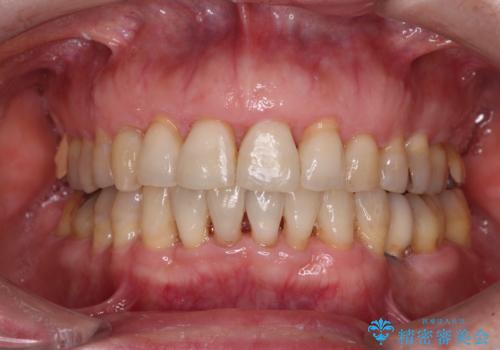

口元の出っ張りとデコボコを改善したい

口元の突出感とデコボコが気になっているとのことでしたが、インプラントが既に3本埋入されていたため、抜歯矯正による口元を引っ込めることができない状況でした。

近医での歯周病治療の影響でブラックトライアングルが発現していたため、IPR(歯と歯の間を削る)で隙間を改善しつつ、インプラントを固定源に歯列全体を後方へ移動させることとしました。